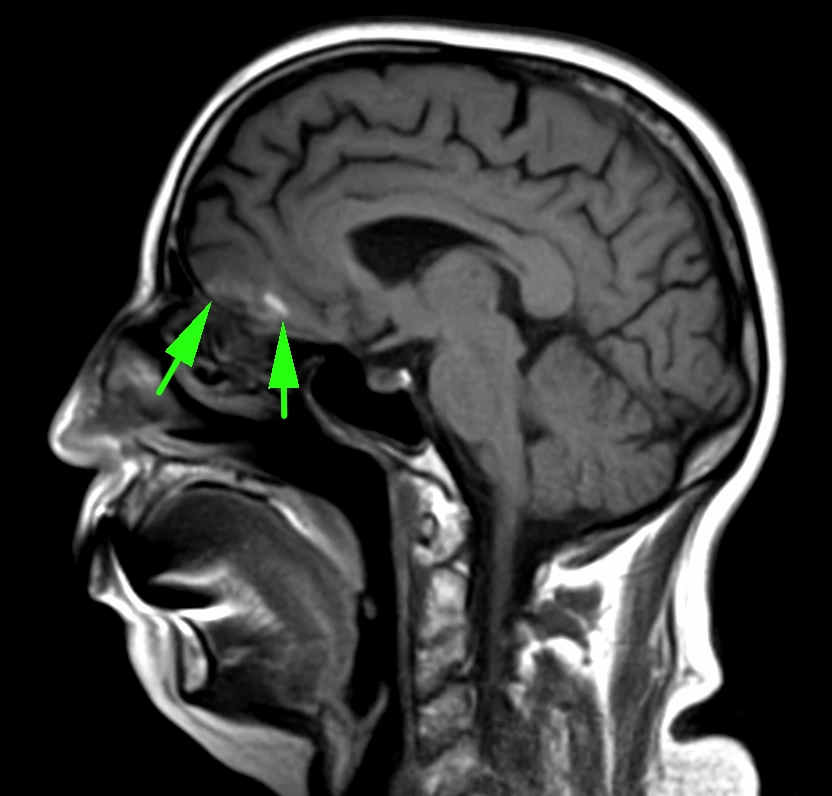

Наконец-то я увидел это воочию! Киста полости Верги, промежуточного паруса, осложнённая гидроцефалией. Из анамнеза: Низкое артериальнео давление, нарушение речи, затуманенное сознание, головная боль, головокружение, в 1989 году перенёс менингит.

А Вы видали такое? Я впервые вижу, раньше только читал в литературе.